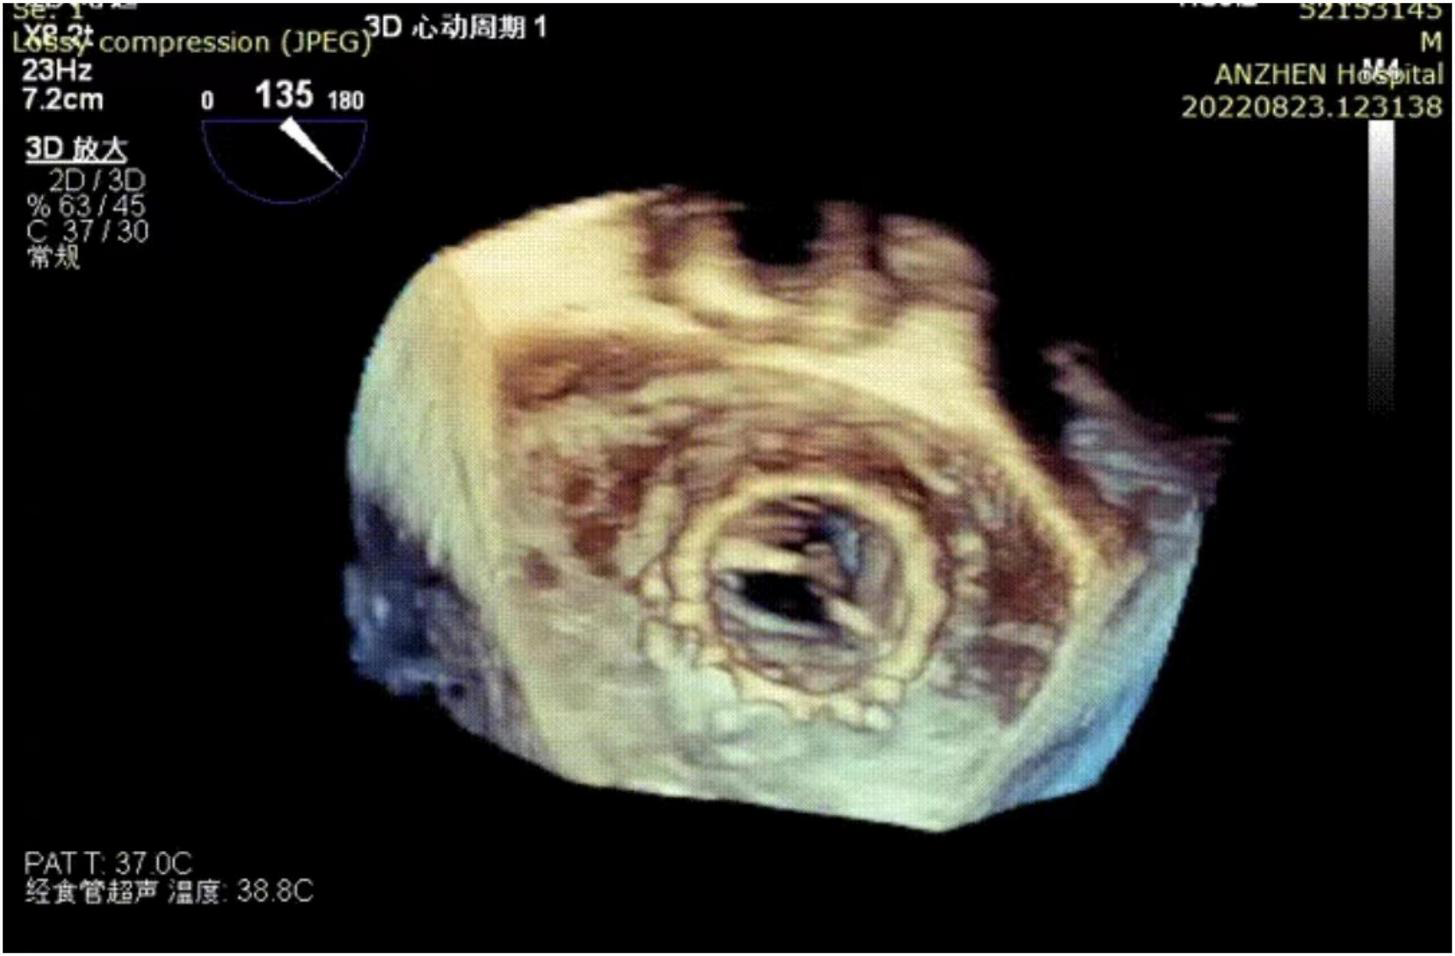

Post-procedural echocardiography could detect neither paravalvular leakage nor aortic or mitral regurgitation. Three-dimensional transesophageal echocardiography showed a good shape of the mitral transcatheter heart valve (Figure 3). Echocardiography showing a mitral valve area of 1.7 cm2 and mitral valve mean gradient of 3 mm Hg and a transaortic gradient valve mean gradient of 13 mm Hg. The post-operative course was uneventful and without complication. The patient was discharged on post-operative day eight. After 2 months of follow-up, the patient’s NYHA class improved to grade 2.

FIGURE 3

Three-dimensional transesophageal echocardiography reconstruction showing the mitral transcatheter heart valve.